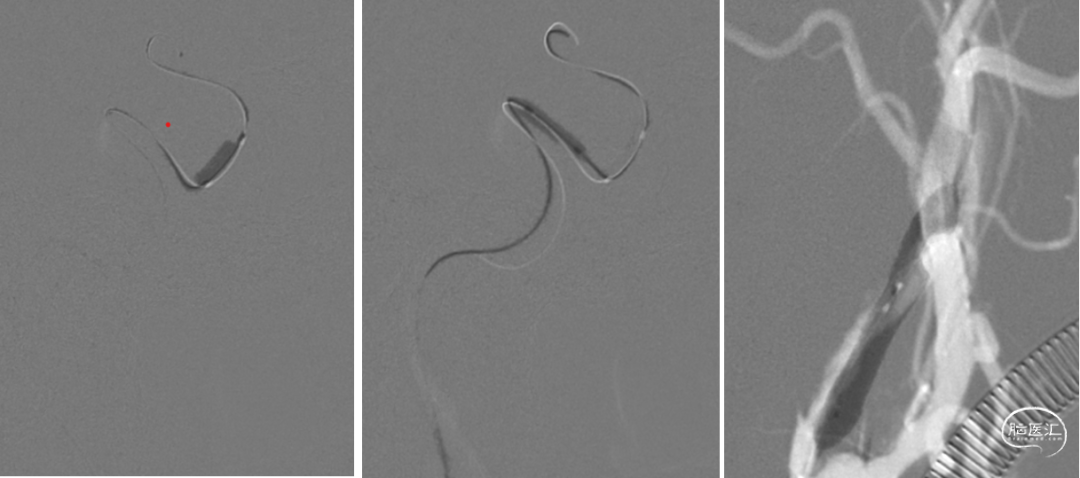

术中过程 :微导管超选到位

术中过程:逐段球囊扩张

术中过程:释放支架过程